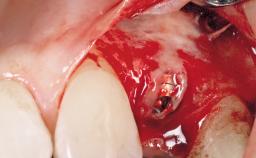

Early Placement of an Implant in a Maxillary Right Central Incisor Site

This 41-year-old female patient was referred to the clinic for the replacement of the right central incisor, since the tooth had developed a root fracture in the long axis that made extraction necessary. The healthy, non-smoking patient was first seen with the tooth still in place. A detailed Esthetic Risk Assessment was performed.The patient was worried about her dental esthetics and had high expectations for a successful treatment outcome from an esthetic point of view. The patient had a medium lip line that displayed parts of the gingiva in the anterior maxilla upon smile.

Bone Volume Deficient horizontally, allowing simultaneous augumentation

Esthetic Risk High